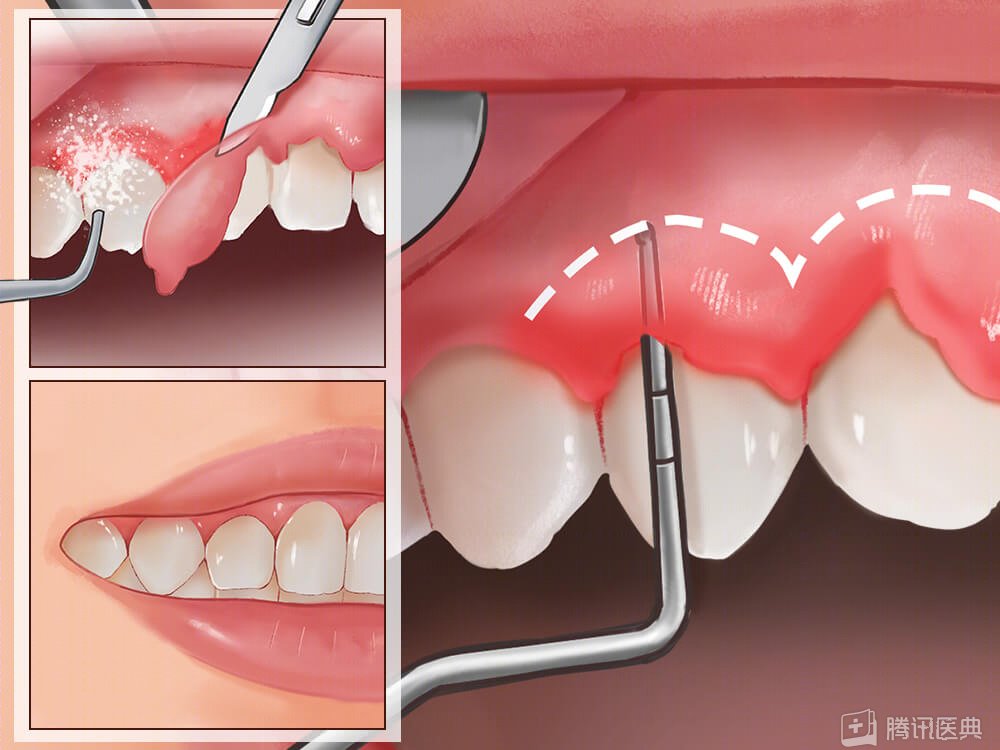

经过多次牙周序列治疗,即全口洁治(洗牙)、龈下刮治、松牙固定术等,最终陈教授成功为她保住了所有牙齿。

比如,如果孕期得了牙周疾病,推荐在孕中期进行必要的牙周干预,如洗牙、脓肿引流、溃疡性牙龈炎的上药冲洗等。

说是瘤,其实是牙龈增生,看起来不太美观,可以通过牙周手术或激光切除。